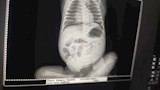

أنقذ الفريق الطبي بمستشفى زاوية الناعورة المركزي في مركز الشهداء بمحافظة المنوفية، حياة طفلة حديثة الولادة تبلغ من العمر 18 يومًا، بعد إجراء جراحة دقيقة ومعقدة في الأمعاء، تكللت بالنجاح، في إنجاز طبي جديد يُضاف إلى سجل مستشفيات محافظة المنوفية.

وخلال الفحص تبين وجود ثقب في الأمعاء الدقيقة للطفلة، ما استدعى تدخلاً جراحيًا عاجلًا لإصلاح الثقب، وأخذ عينات من الأمعاء، ثم إجراء توصيل بين الأمعاء الدقيقة وجدار البطن، وهي من العمليات النادرة التي تتطلب مهارة عالية في جراحات الأطفال.